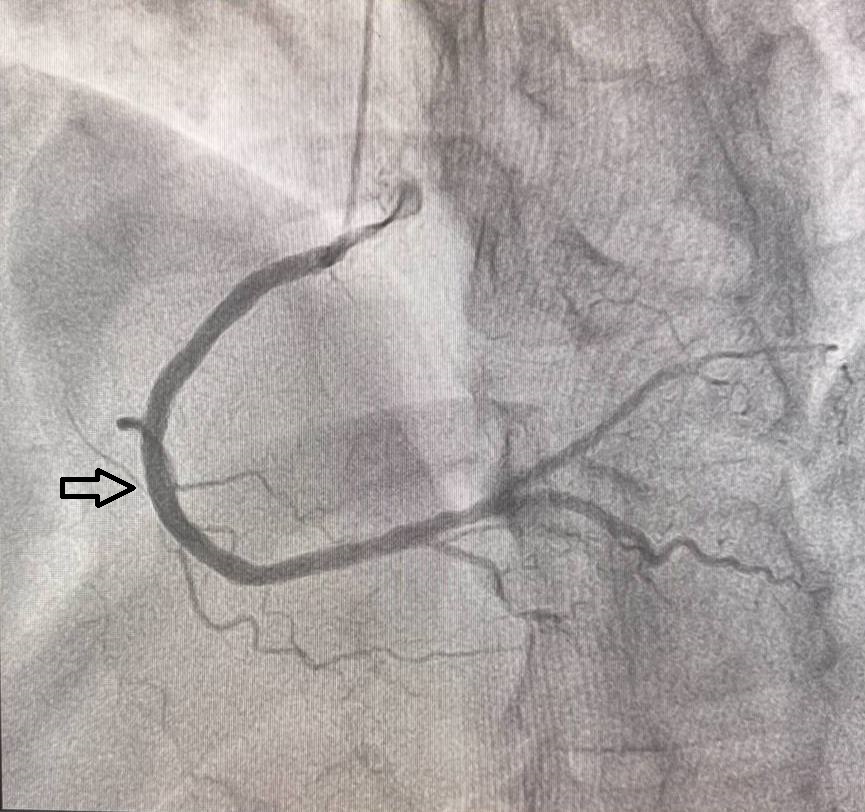

The primary endpoint was the incidence of restenosis at 12 months, assessed by coronary angiography. Restenosis was defined as ≥50% diameter stenosis in any coronary artery segment at the site of the stent. Angiography was performed in two projections both before implantation and after 12 months, using the same angle to ensure consistency.Secondary Outcomes

One-Year Follow-UpCoronary Angiography Results

Of the 60 patients who received colchicine (0.5mg daily), restenosis was observed in 4 patients (6.7%).

In the placebo group, restenosis was observedin 11 out of 60 patients (18.3%).

The use of colchicine (0.5 mg daily) significantly reduced the rate of restenosis compared to the placebo group, with a statistically significant p-value of 0.02. This result is consistent with recent meta-analyses showing that colchicine’s anti-inflammatory properties can help reduce vascular inflammation, a key factor in restenosis and other cardiovascular events.The ESC (European Society of Cardiology) and ACC (American College of Cardiology) guidelines recommend anti-inflammatory therapies for improving outcomes in patients with atherosclerotic cardiovascular disease (ASCVD). Colchicine’s role in reducing inflammation following PCI aligns with these recommendations, particularly for high-risk populations, such as patients with diabetes and vascular calcification.In the colchicine group, the restenosis rate was significantly lower across all vascular territories, with no restenosis in LAD and LCX, and a minimal rate in RCA. These results are in line with the COLCOT (Colchicine Cardiovascular Outcomes Trial) and other large studies, which demonstrated that colchicine reduces major adverse cardiovascular events (MACE) and improves long-term outcomes.Patients with vascular calcification, traditionally at higher risk for restenosis, experienced considerable benefit from colchicine therapy. This finding supports the ESC Guidelines for the Management of Chronic Coronary Syndromes, which emphasize personalized treatment strategies targeting inflammation in high-risk patients. In contrast, the placebo group showed a higher rate of restenosis, especially in vessels with significant calcification and among diabetic patients, consistent with ACC/AHA guidelines highlighting increased restenosis risk in these subgroups.These findings suggest that colchicine could be a valuable adjunctive therapy in PCI to reduce restenosis, particularly for patients at high risk of adverse outcomes. Future studies with larger cohorts are needed to confirm these results and optimize patient selection for colchicine therapy.